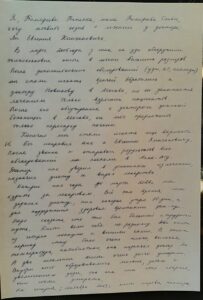

Я, Тимофеева Татьяна, мама Тимофеева Славы, хочу оставить отзыв о лечении у доктора Ли Евгения Хынчановича.

В марте в 2015 года у сына на УЗИ обнаружили эхинококковые кисты в печени больших размеров. После дополнительных обследований (УЗИ, КТ, анализы), мы стал искать врачей. Обратились к доктору Новикову в Москве, но он занимается лечением только взрослых пациентов. После обсуждения с доктором детской поликлиники, единственное что он мог предложить — только пересадку печени.

Конечно мы стали искать другие варианты лечения, и Бог направил нас к Евгению Хынчановичу. После звонка, консультаций и отправки результатов всех обследований мы поехали в Алма-Ату. Доктор нас уверил в успешном излечении, назначил диету и выдал лекарство.

Каждый полгода до марта 2022 мы ездили за лекарством. Все это время сын держал диету, каждое утро пил «Ю-дин», а также временами » Ден-су» для поддержания здоровья. Надо сказать, что это был большой и трудный путь. Кисты вели себя по-разному. Две кисты из четырех лопнули и вышли сами. В это период сыну было очень плохо, высокая температура, антибиотики, как назначал доктор Ли. Две оставшиеся кисты умирали очень долго. Внутри кист образовывались мелкие, затем с увеличением дозы, так как сын стал старше, они стали умирать.

На сегодня : сентябрь 2023 года, все кисты мертвы, анализы в порядке, самочувствие нормальное.

Самое главное, что лечение не повлияло развитие и здоровье ребенка. Сын все это время занимался спортом, участвовал на соревнованиях, учился без перерывов в июле.

Фото УЗИ приложу, самое первое и на сегодняшний день.

От все нашей семьи выражаем большую благодарность доктору Евгению Хынчановичу.

Не сомневайтесь в этом лечении, напротив будьте уверены, что это самый лучший вариант излечения от этих страшных заболеваний.

Если вам хочется задать мне вопросы, всегда рада ответить тел: 89630935871 Татьяна Тимофеева, г. Магнитогорск, Челябинская область.